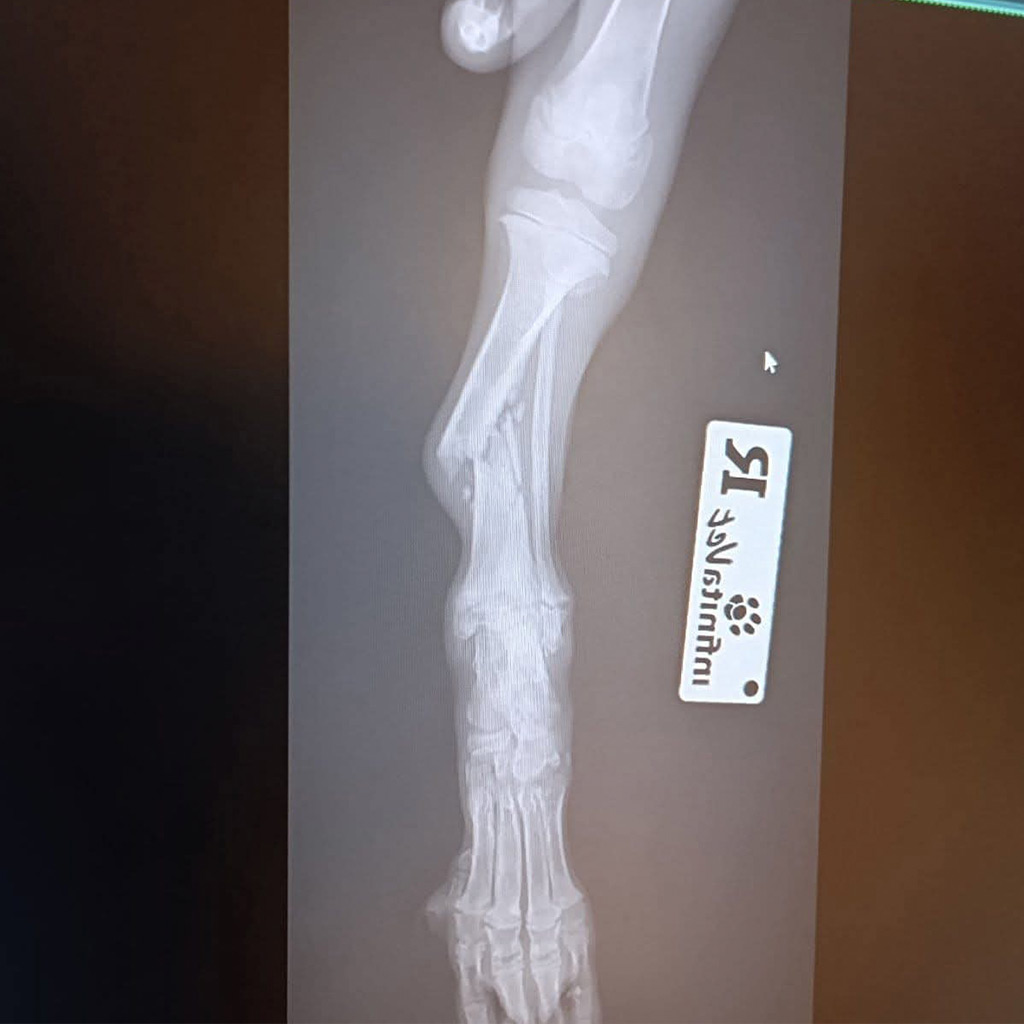

Zum Glück wurde Luca gefunden und sofort in eine Tierklinik gebracht. Dort folgte die erschütternde Diagnose: Ein Vorderbein und ein Hinterbein sind gebrochen. Die Röntgenbilder bestätigten das ganze Ausmaß ihrer Verletzungen.

Die Fraktur am Hinterbein kann ohne Operation ausheilen, hier ist strenge Schonung ausreichend.

Doch das Vorderbein ist so schwer verletzt, dass eine Operation dringend notwendig ist. Um eine stabile und dauerhafte Heilung zu ermöglichen, muss ein Metallimplantat eingesetzt werden. Nur so hat Luca die Chance, später wieder schmerzfrei zu laufen und ein normales Hundeleben zu führen.